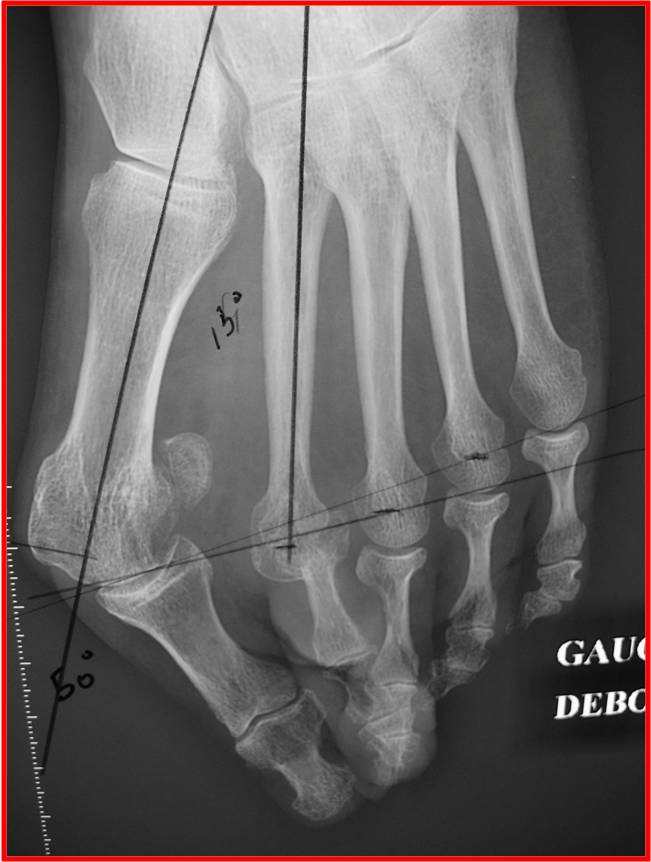

Hallux Valgus

C’est le classique « oignon » (ou « bosse » ou exostose) qui correspond à la déviation en dehors du gros orteil.

Il s’agit d’une déformation complexe touchant l’os, les muscles, les capsules articulaires et les ligaments.

2. Ostéotomie de Scarf du 1° métatarsien pour réaligner l’os, maintenue par 2 mini-vis ;

3. Ostéotomie de varisation +/- raccourcissement de la 1e phalange du gros orteil, maintenue par une micro lame-plaque ;